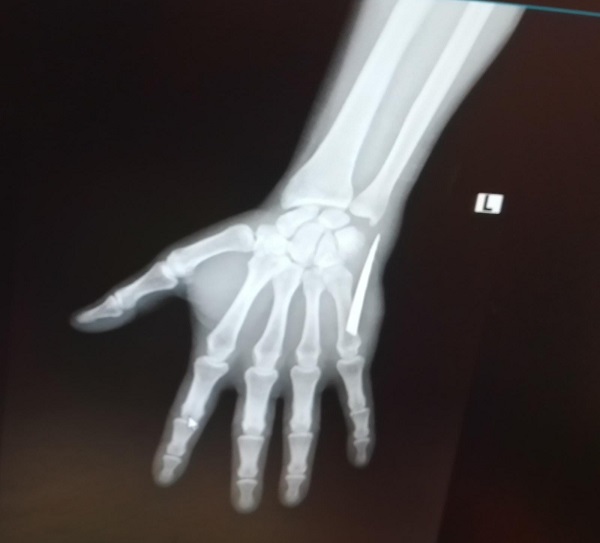

2 aydır haberi bile yoktu! Röntgen çekilince hayatının şokunu yaşadı

Zonguldak’ta iki ay önce eline girdiğinden haberi olmadığı bıçak parçasıyla 2 ay boyunca yaşayan tır şoförü Doğukan Köseli, çektirdiği röntgen filminde hayatının şokunu yaşadı. Acısını dindirmek için mücadele veren genç adam, iddialara göre kendisine bu acıyı yaşatanlara karşı hukuk mücadelesi başlatacak.